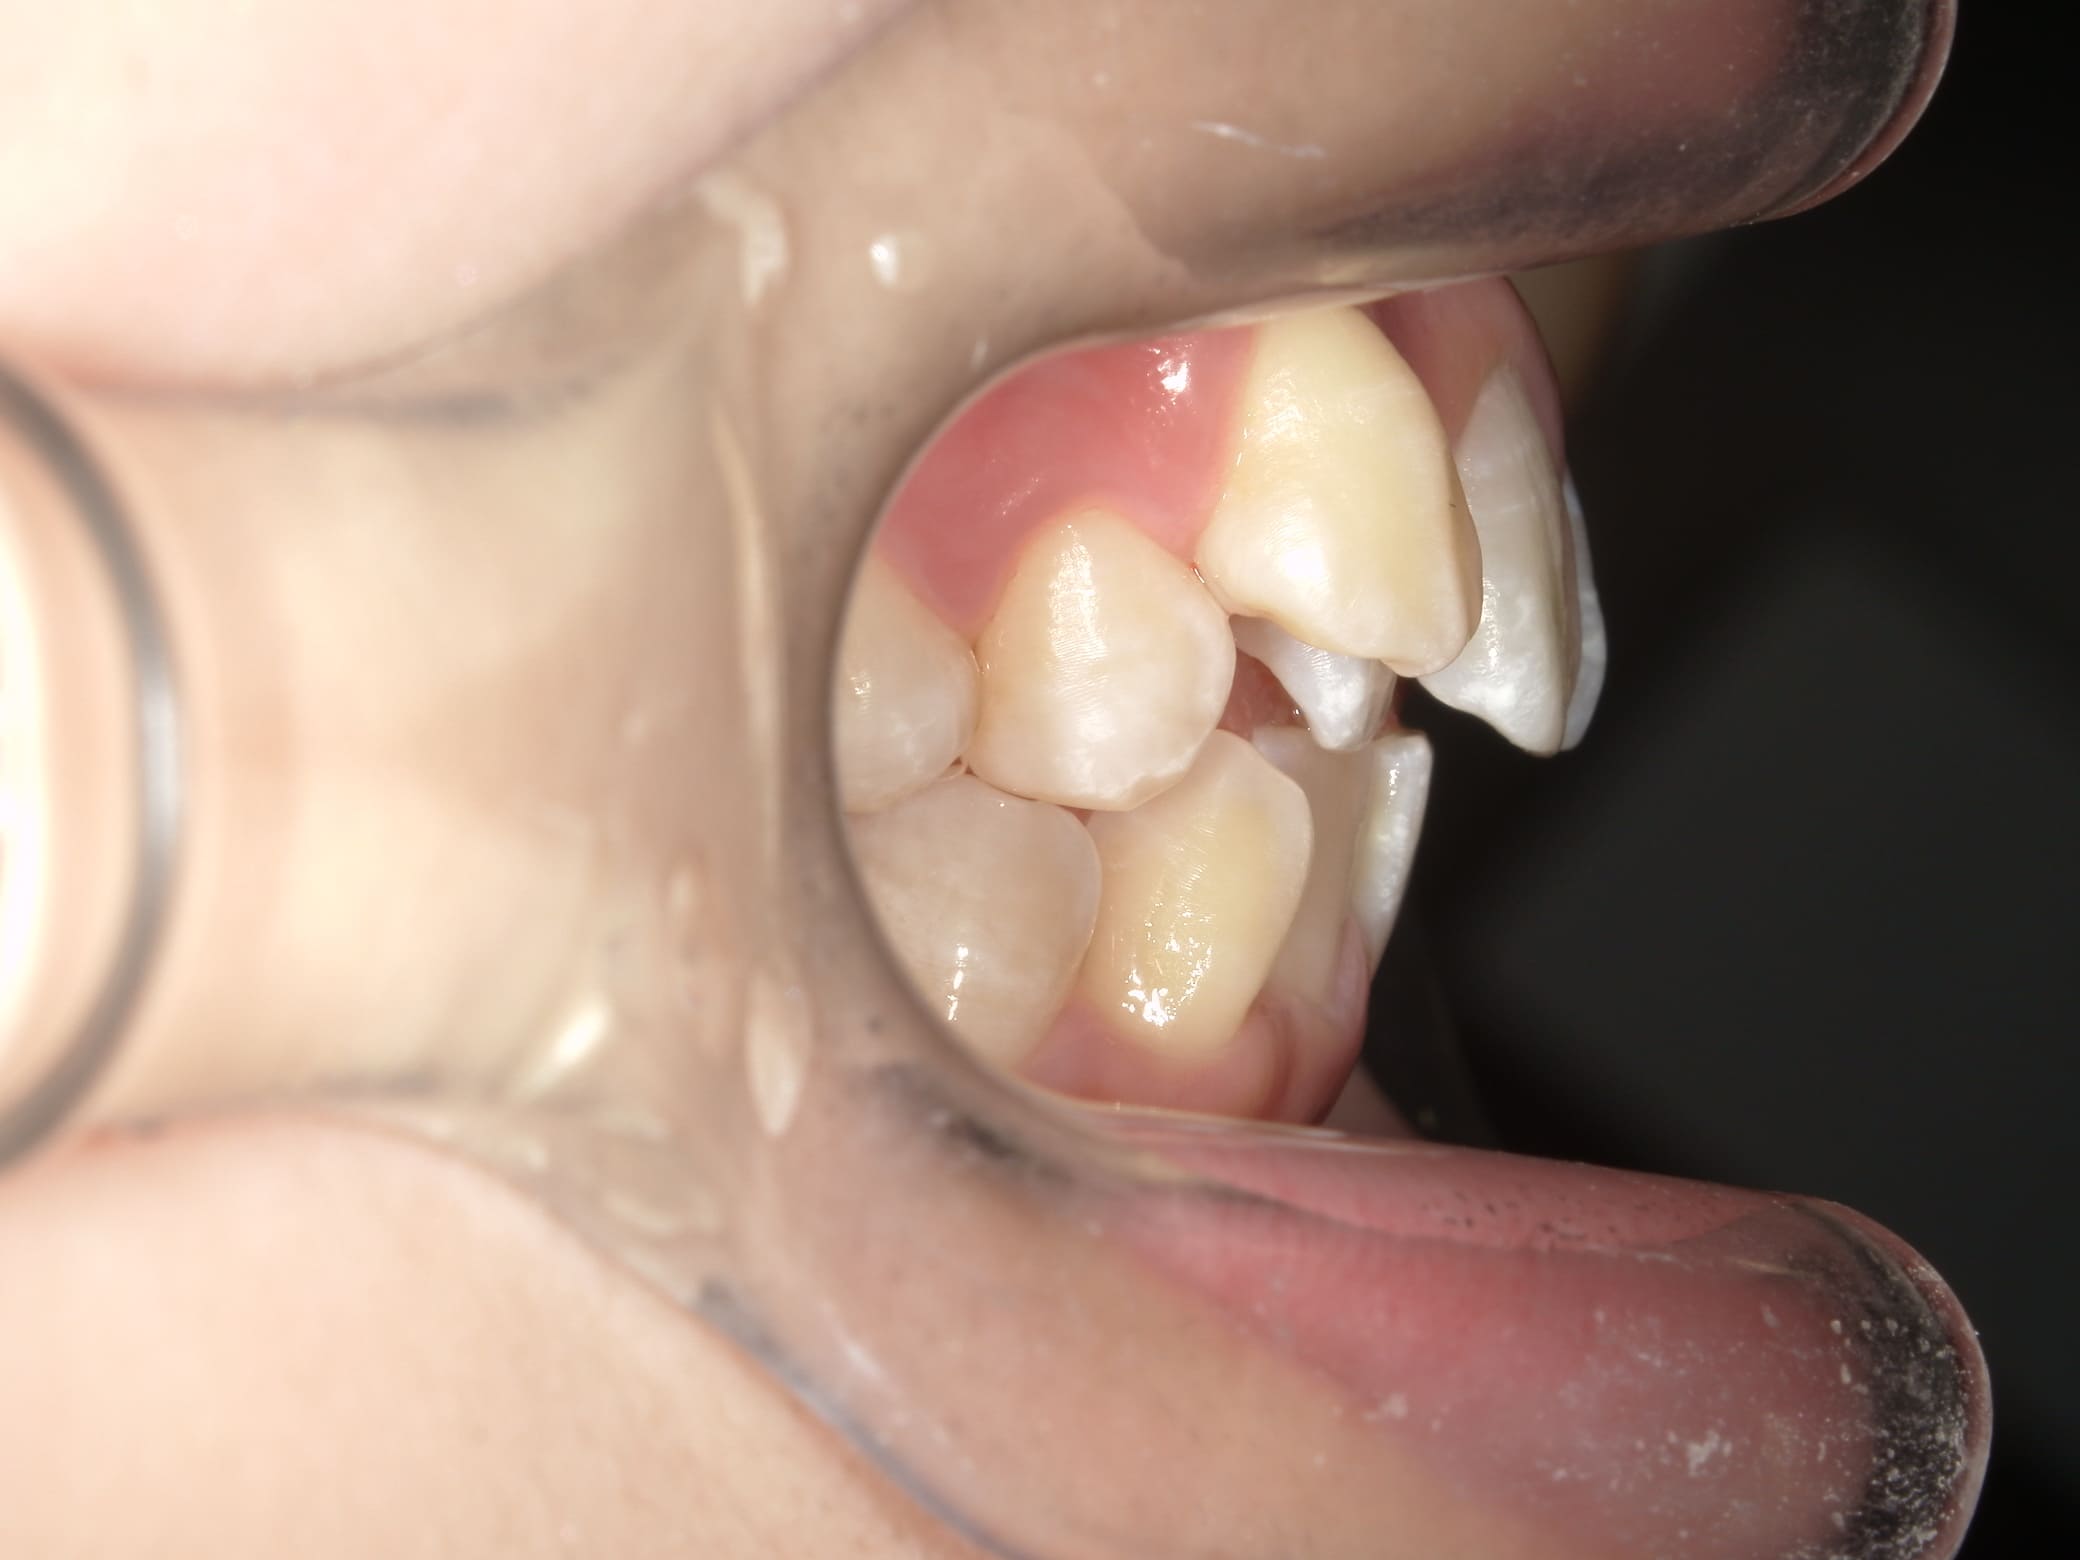

| 年齢・性別 | 21歳 |

|---|---|

| 主訴 | 叢生が気になる・前歯に埋伏歯がある |

| 治療期間・回数 | 6ヶ月 |

| 費用 | 935,000円 |

| 上顎の左側3番が埋伏していたため、上顎左右の3番および親知らずを抜歯し、矯正治療を行いました。 治療開始からおよそ6ヶ月で歯列が整い、審美的にも機能的にも良好な結果が得られた症例です。 |